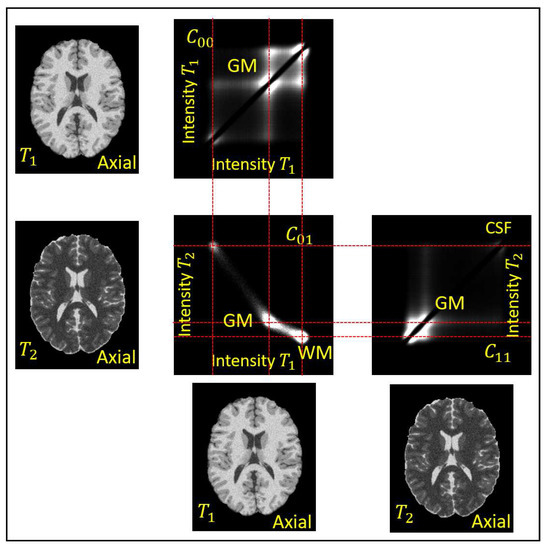

The first order term provides a linear approximation of the non-uniformity within a spherical neighborhood of radius . The effects of the second and higher order terms are neglected within . The statistical representation of images and is based on intensities and within neighborhood . Their counts give the co-occurrence statistics as [35,43]:

They give the auto-co-occurrences for and the joint-co-occurrences for . The auto-co-occurrences are dominated by their diagonal entries and thus they are weighted down with the sigmoid . The different tissues, or tissues interfaces, of the anatomic images are assumed to correspond to distinct modes of the co-occurrence statistics. An example of the co-occurrences of a pair of and BrainWeb phantom images [37] is in Figure 4. A median filtering is applied to to remove the high frequency noise . The objective of the analysis is to separate the remaining two products in , present in Equation (9) to obtain the factors and , respectively.

Figure 4.

The auto-co-occurrence statistics and the joint-co-occurrence statistics of a and a image of the BrainWeb phantom without non-uniformity, , and with noise of [37]. The densities in the statistics are displayed in logarithmic scale. The individual distributions of the Gray Mater (GM), White Matter (WM), and Cerebrospinal Fluid (CSF) are apparent.